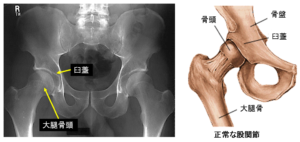

股関節の構造股関節のしくみ股関節の痛み関節の痛み人工関節ドットコム。

股関節の構造と代表的な疾患について - 医療法人相生会 福岡みらい病院。

変形性股関節症 - 古東整形外科・リウマチ科。